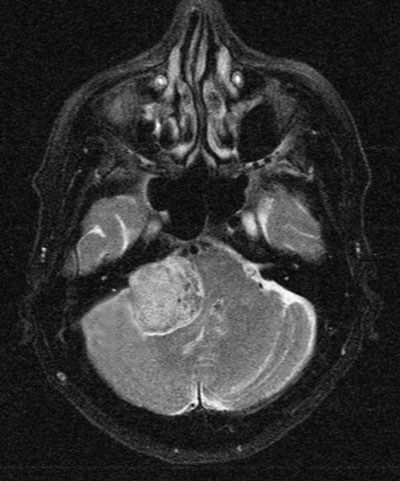

Figure 6: Brain MRI showing a large posterior fossa tumour most likely an acoustic neuroma.

Vestibular schwannomas or acoustic neuromas (Figure 6) are more often seen in the eye clinic for management of postoperative complications than for diagnosis. They usually present to the ENT or neurology clinics because of hearing loss, tinnitus or balance problems. Because these tumours alter the CSF composition or block the fourth ventricle they can also produce papilloedema. Complete surgical removal is seldom achieved and a facial palsy or facial paralysis is a common post operation problem. In addition, because the seventh nerve carries the secreto-motor supply to the lacrimal gland through its greater superficial petrosal branch, a dry eye will ensue.